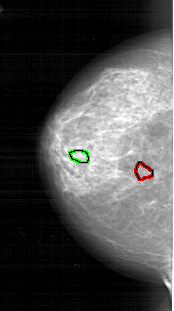

A_1744_1.LEFT_CC

LEFT_CC LINES 5281 PIXELS_PER_LINE 2956 BITS_PER_PIXEL 12 RESOLUTION 43.5 OVERLAY

FILE: A_1744_1.LEFT_CC.OVERLAY

TOTAL_ABNORMALITIES 1

ABNORMALITY 1

LESION_TYPE CALCIFICATION TYPE PLEOMORPHIC DISTRIBUTION CLUSTERED

ASSESSMENT 4

SUBTLETY 2

PATHOLOGY BENIGN

TOTAL_OUTLINES 1

BOUNDARY

ABNORMALITY 2